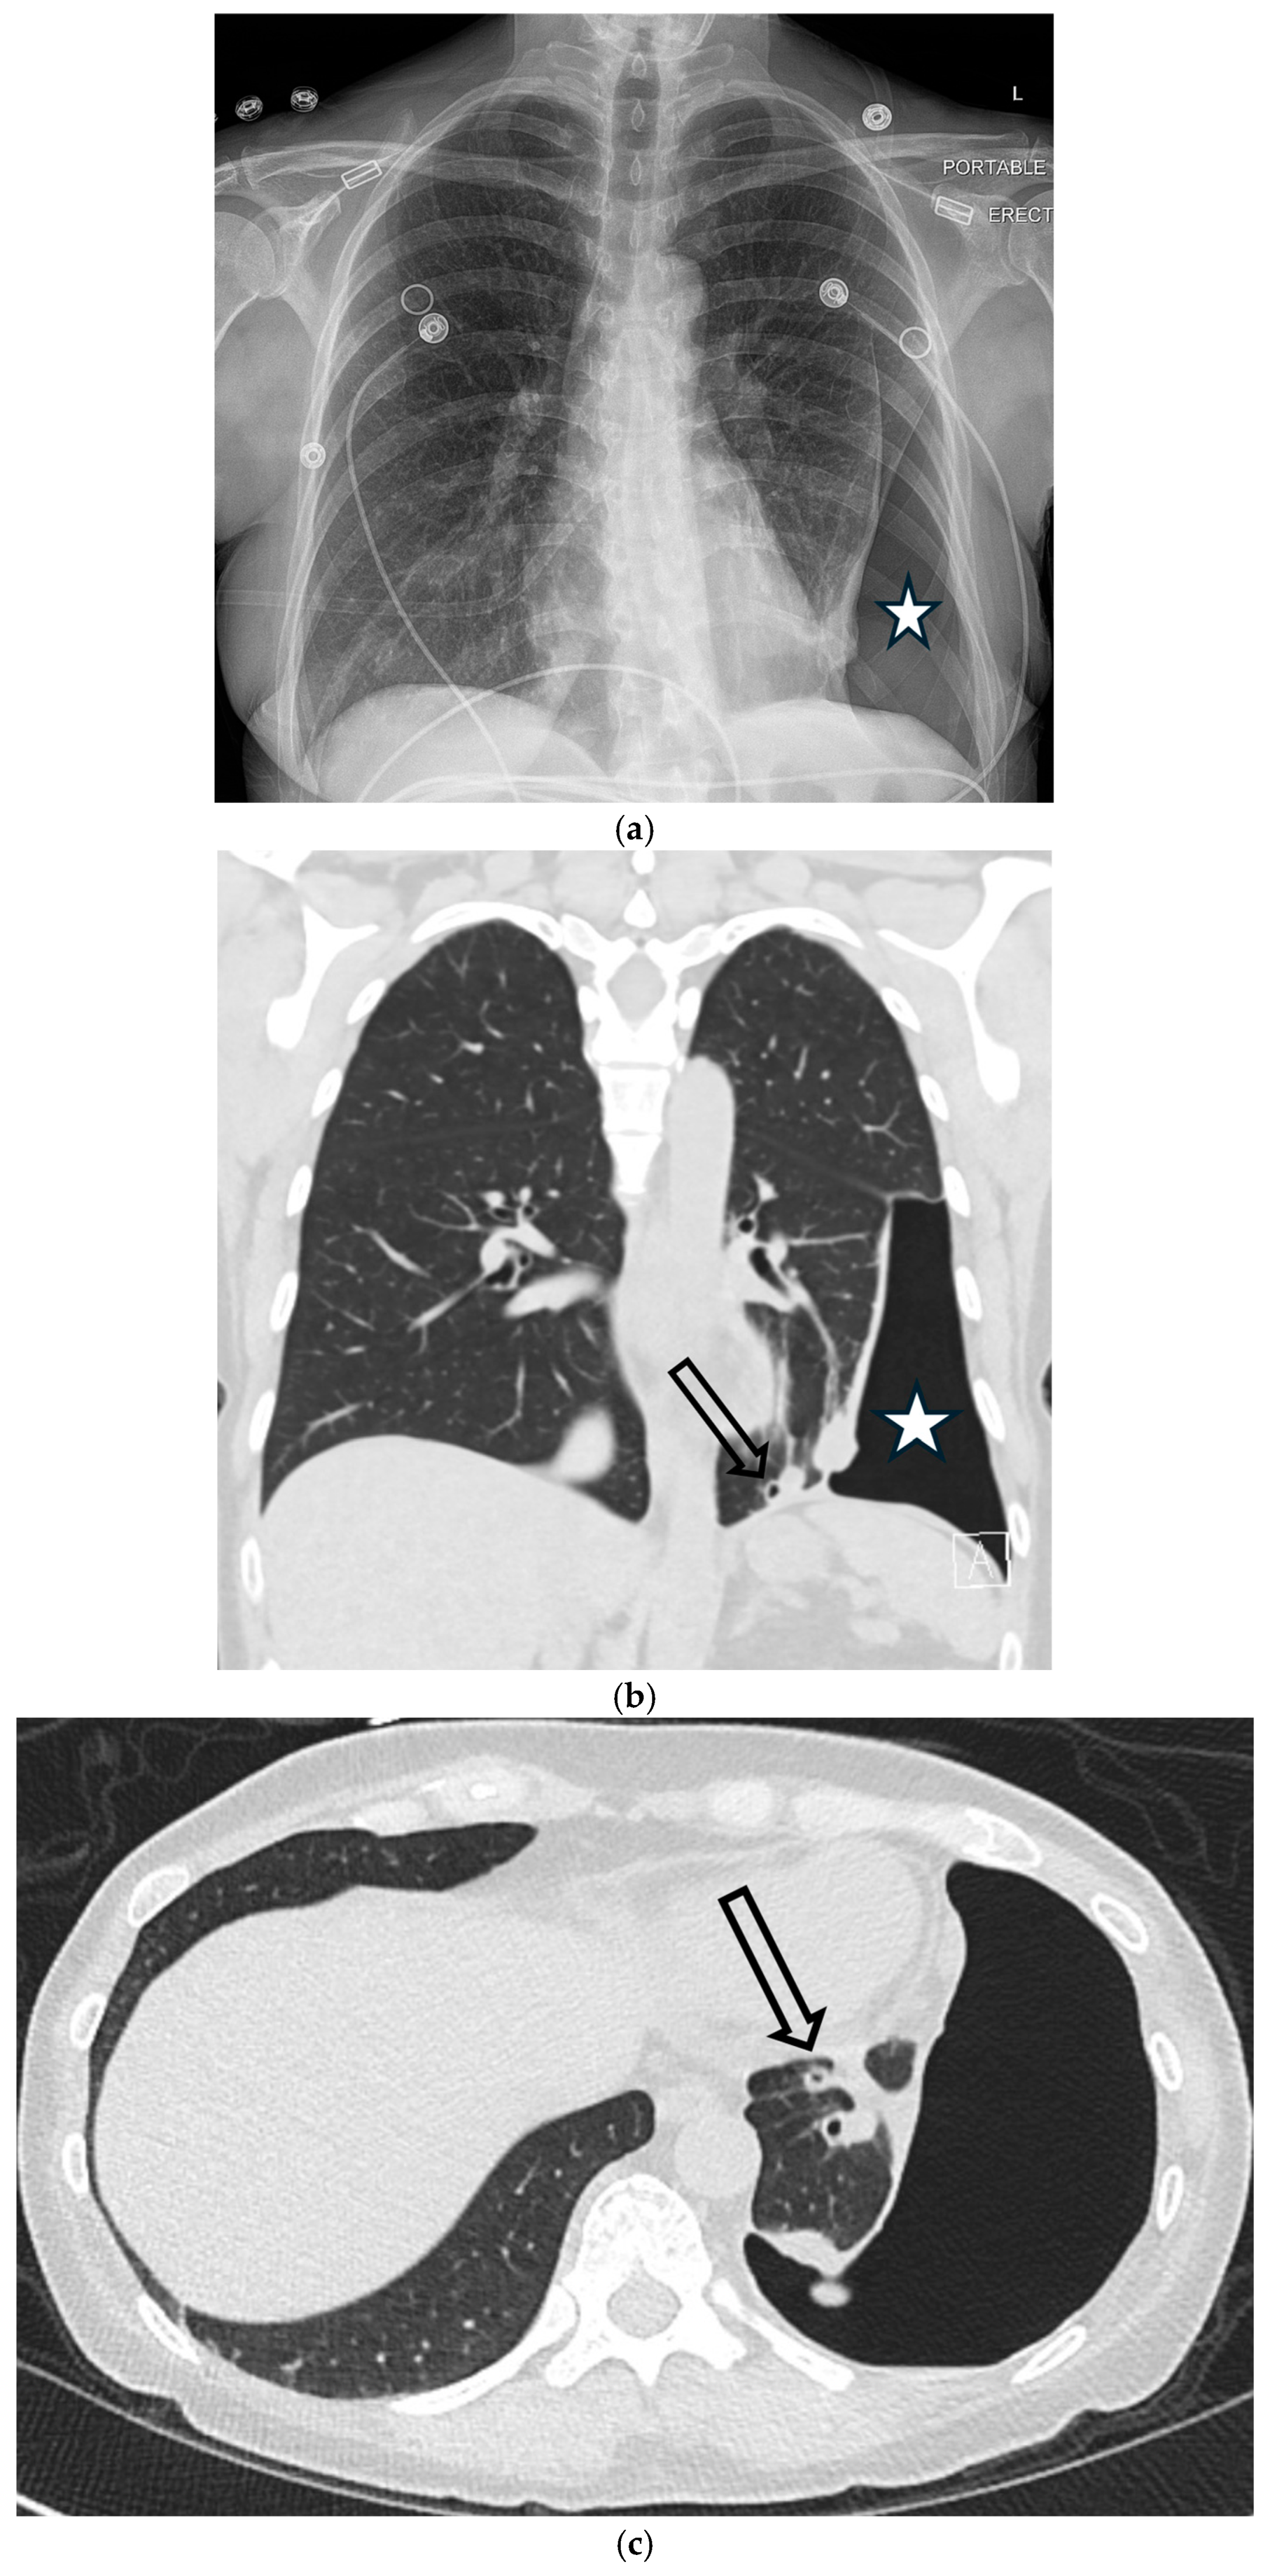

5.1.2. COVID-19 Pneumonia

5.1.3. Pneumocystis jirovecii Pneumonia (PJP)